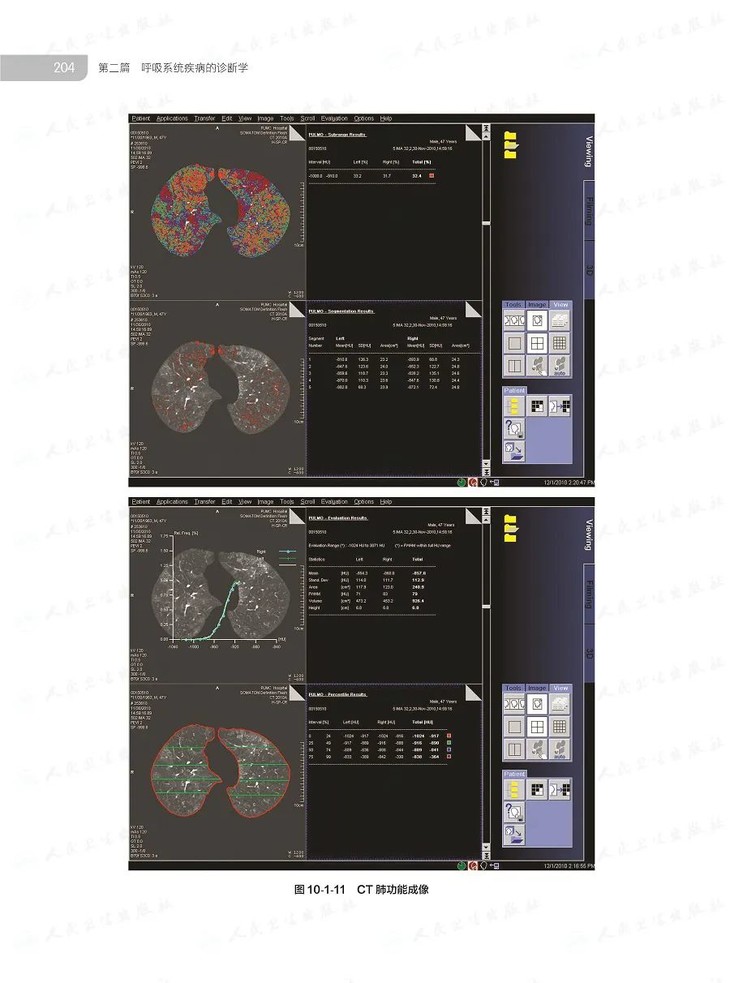

本书共4篇43章,316万字,萃取我国殿堂级呼吸医学专家的临床思维和诊治经验,对我国呼吸病学领域的基本理论技术及先进的临床实践和科研成果等进行了系统阐述,将国际临床新进展、诊治新技术、新指南标准等加以总结,较全面地反映了国内外呼吸病学的发展水平,基础与临床紧密结合,内容精准实用,配以丰富精美图片,是中国PCCM医生必备的案头工具书。